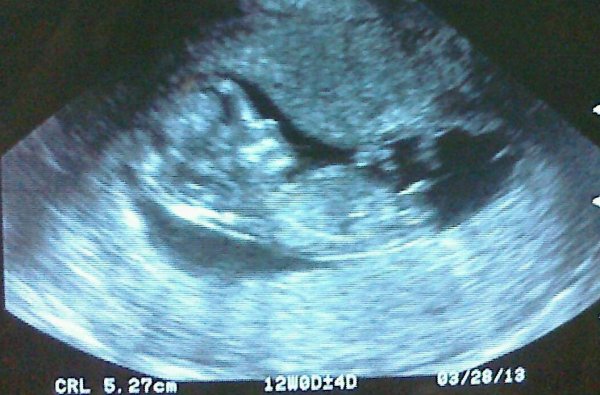

Hi everyone! This is from my 12 week scan. I was exactly 12 weeks, baby measured 12 week 4 days. Not sure if that makes a difference. :)

Found at at 15 weeks, he's a boy!!